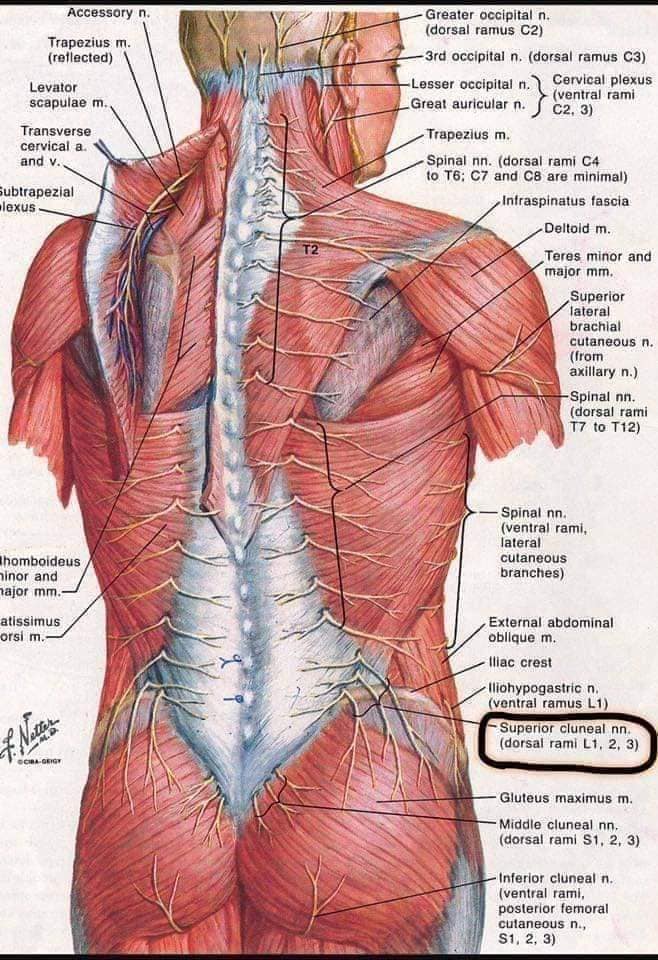

Шийні м'язи

Шийні м'язи мають важливе значення для підтримки голови і забезпечення її рухів.

М'язи задньої групи

М'язи, що розширюють шию: М'язи, що розширюють шию: включають трапецієподібний м'яз, який бере участь у піднятті плечей і розширенні шиї.

Спинні м'язи

Спинні м'язи виконують функції підтримки хребта, а також дозволяють здійснювати рухи тулуба.

Поверхневі спинні м'язи

М'язи, що піднімають лопатку: Трапецієподібний м'яз: великий м'яз, що покриває верхню частину спини. Його функція - підтримка і рух лопаток, а також забезпечення стабільності хребта.

М'язи, що ведуть лопатку до хребта: Широкий м'яз спини: великий м'яз, що розташований в нижній частині спини. Він відповідає за рухи плечей і лопаток, а також за розширення верхньої частини тулуба.

Глибинні спинні м'язи

М'язи, що забезпечують стабільність хребта: М'язи, що розташовані між хребцями: включають мускулатуру, яка забезпечує стабільність і підтримку хребта, а також дозволяє здійснювати рухи хребта.

М'язи, що здійснюють ротацію та нахили

М'язи, що забезпечують ротацію хребта: Ротаційні м'язи: допомагають у здійсненні обертальних рухів тулуба, а також у підтримці рівноваги і стабільності хребта.